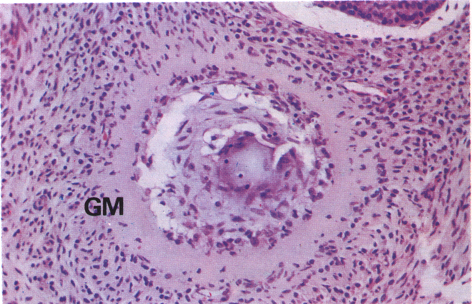

What is this?

Follicular atresia